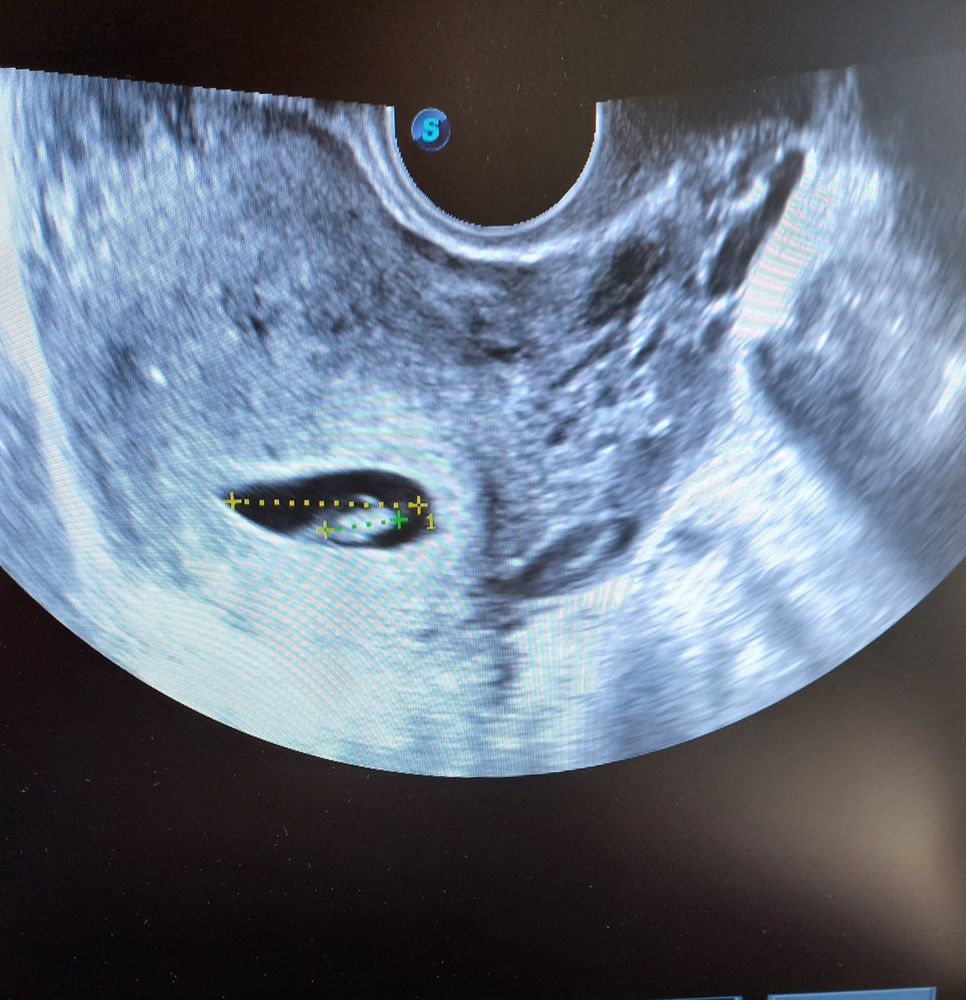

Первое узи 7 недель

УЗИ, КТГ, доплерСегодня была первый раз была на узи, все хорошо. Поставили 6 недель 6 дней .Движение есть сердцебиение тоже:)

Единственное в заключении однородное анэхогенное образование 25×23 мм. Киста правого яичника.

Сейчас на узи снимок смотрю эмбрион вижу, и справа внизу что-то тоже. Это и есть киста? Или анэхогенное образование?А то муж шутит, говорит может второго просмотрели;)